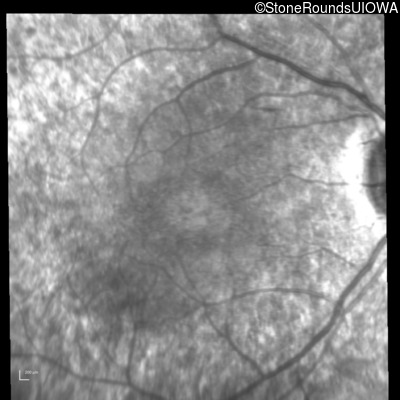

Infrared Fundus Photograph - Right - 20/25 -2

Exemplar